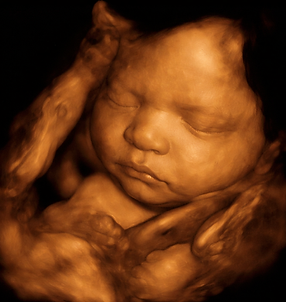

En FEMSALUD contamos con una sección especializada dedicada a brindarte información detallada sobre los diversos tipos de imágenes ginecológicas y obstétricas que realizamos. Nuestro compromiso es ofrecerte estudios precisos y confiables, con tecnología de punta y personal altamente capacitado, para acompañarte en cada etapa de tu salud femenina y reproductiva.